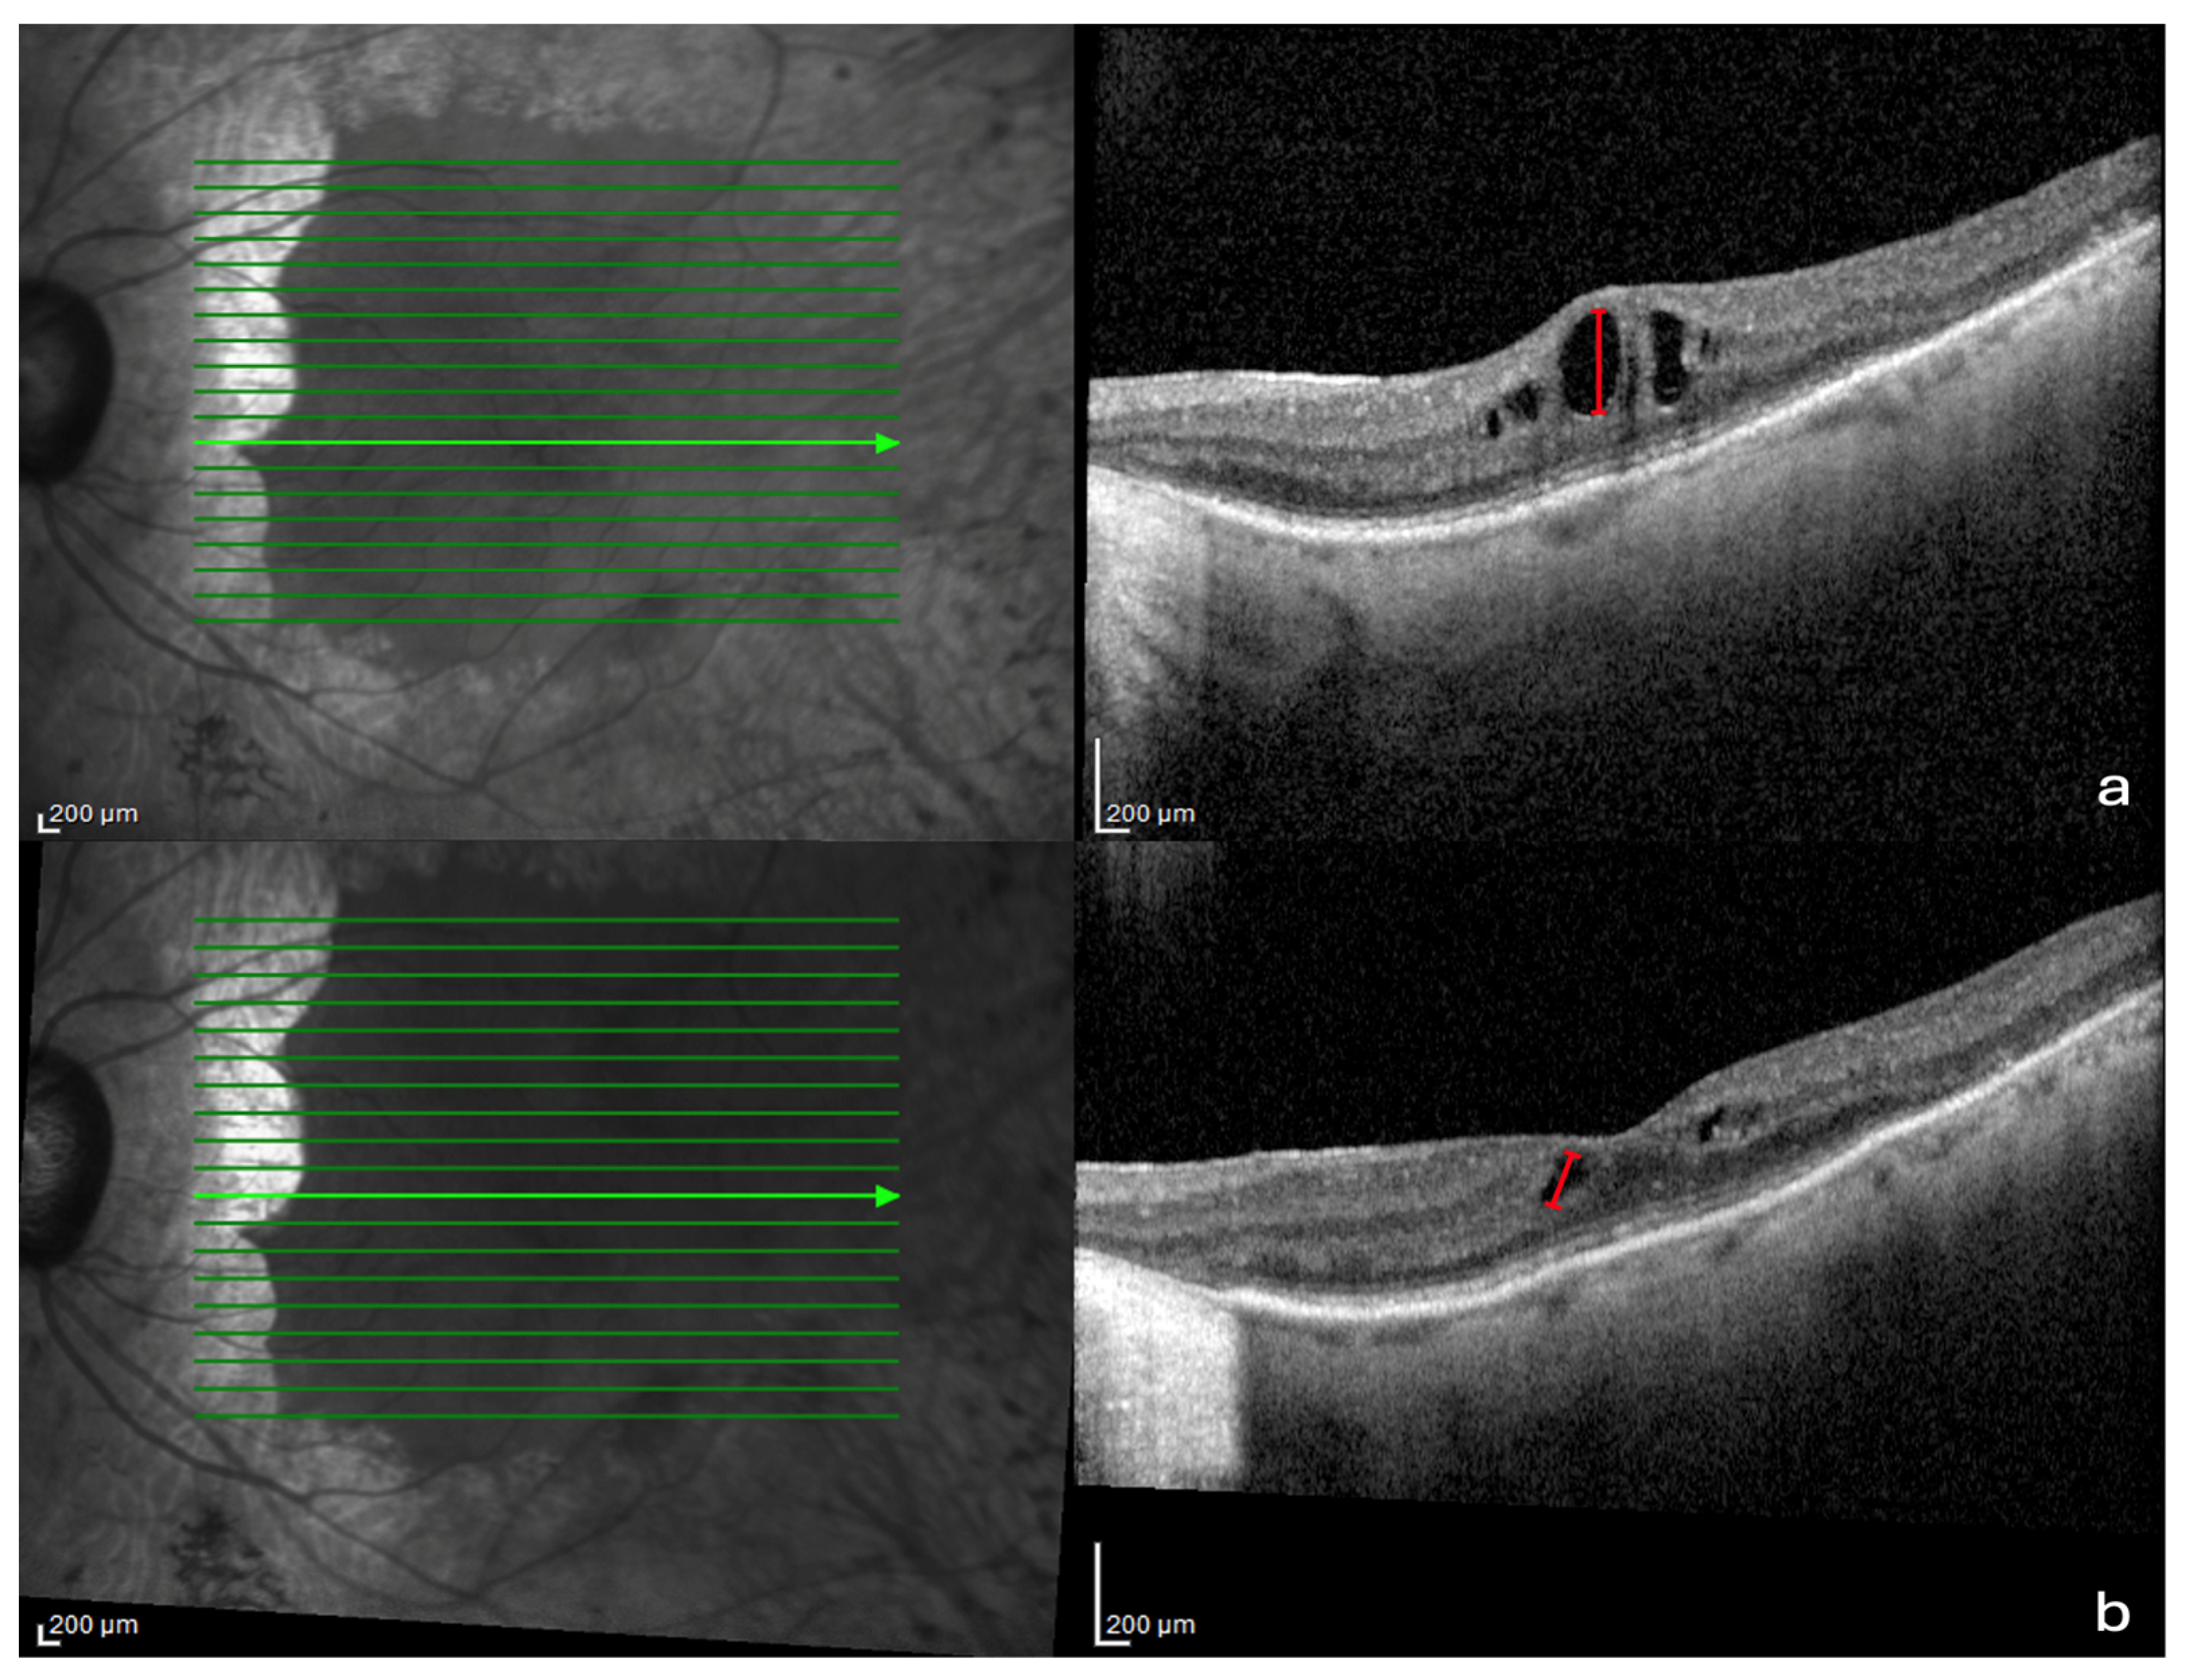

- Eyes with preserved sub-foveal EZ at V1 and V2 observed by OCT scans.